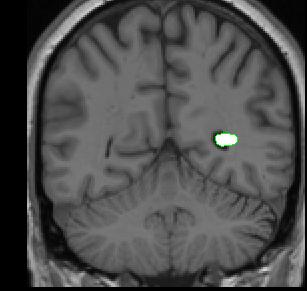

The histogram method is used to create outlines for the lateral ventricles. One histogram is needed to determine the CSF/white matter border, and another is used to define the CSF/gray matter border. A separate circle and histogram should be generated for each ventricle.

lateral-ventricle

Part I - Anterior portion of lateral ventricles

1. Draw a small circle that is half-way in the CSF from the center of the ventricle and and half-way in the white matter from the corpus callosum.

2. Extract the box ( press "e")

3. Generate a histogram (press "f")

4. Extract the lateral ventricle outline from the outside (press "e")

5. Clean the stray pixels and extract from the inside of the ventricle by pressing "I"

histogram